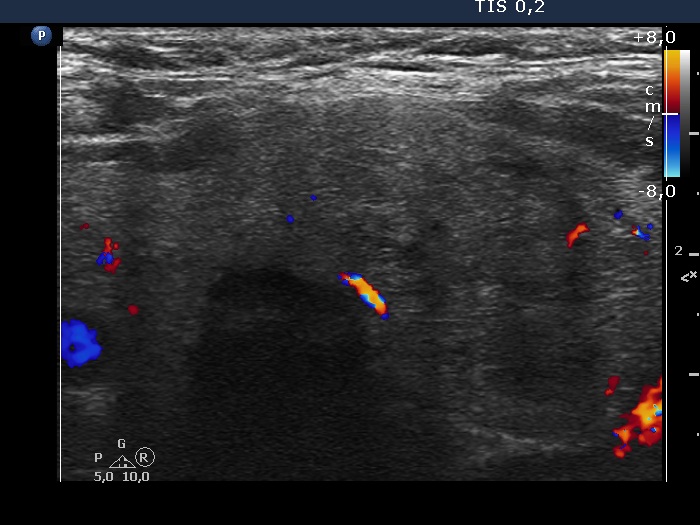

The borders of the nodule - case 2019 (ultrasonographic picture 3)

Left lobe, transverse scan, color Doppler mode. The vascularization is decreased.